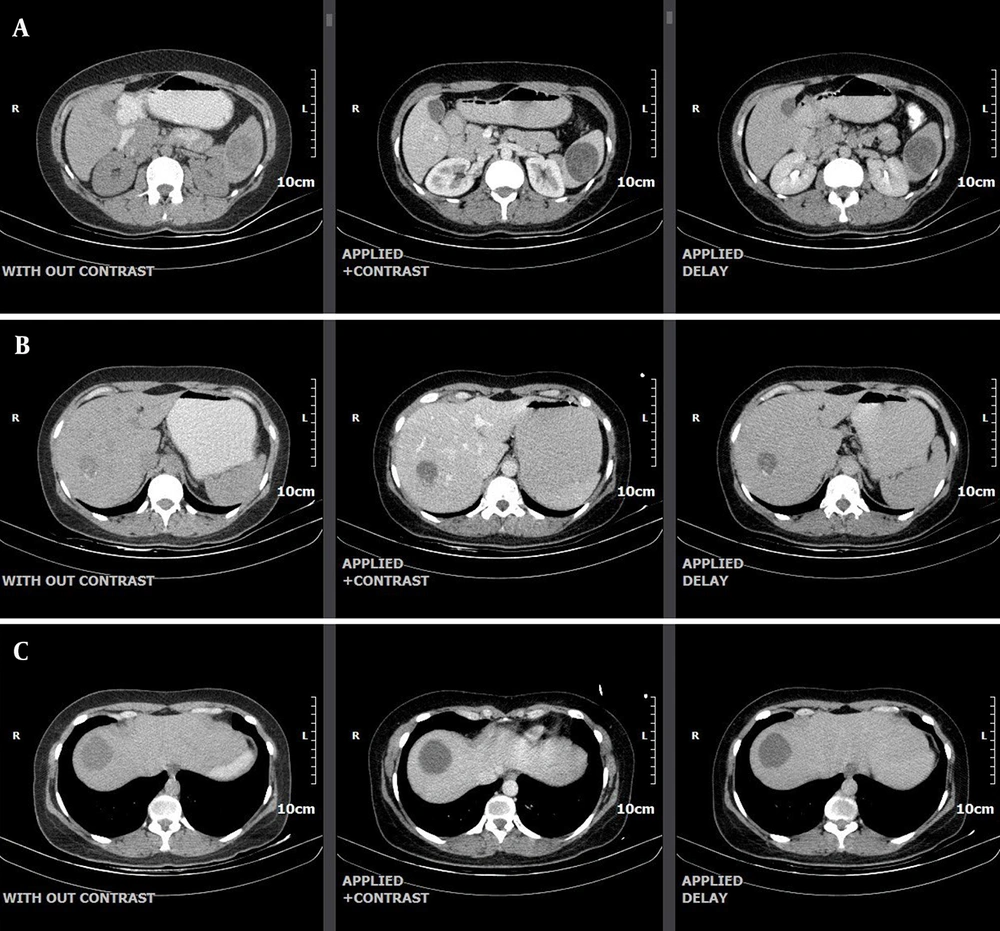

A 26-year-old female patient presented to our hospital with a 3-month history of progressive pain and swelling in the anterosuperior neck, predominantly on the right side. On the patient’s physical examination, a soft, mobile nodule approximately 3 × 2 cm in size was palpated in the right lobe of the thyroid gland. Cervical lymphadenopathy was detected, and examinations of other systems were normal. Blood tests and thyroid tests were within normal limits. The thyroid US revealed a hypoechoic, fluid-filled lesion with internal echoes and thick internal septations, measuring 41 × 36 × 28 mm and with a volume of 22 cc, suggestive of a conglomerate necrotic lymph node (Level III-IVa, Figure 1). Additionally, a hypoechoic nodule, wider than tall, with well-defined borders and peripheral and punctate calcifications measuring 17 × 13 mm was observed (TIRADS V, Figure 2). The FNA of this nodule was suspicious for PTC. Consequently, the patient underwent bilateral total thyroidectomy. No intraoperative and postoperative complications developed. After surgery, the patient was prescribed albendazole 40 mg twice a day, and her symptoms improved. The patient is being followed up without any recurrence. A CT scan of the chest, abdomen, and pelvis performed after total thyroidectomy revealed evidence of hydatid cysts in the liver and spleen but no hydatid cysts in the lungs (Figure 3A - C ).

A, computed tomography (CT) images demonstrate a hydatid cyst measuring 43 mm in diameter in the spleen; B, computed tomography (CT) images demonstrate a hydatid cyst measuring 32 mm in diameter in segment 7 of the liver; C, computed tomography (CT) images demonstrate a hydatid cyst measuring 38 mm in diameter in segment 8 of the liver.